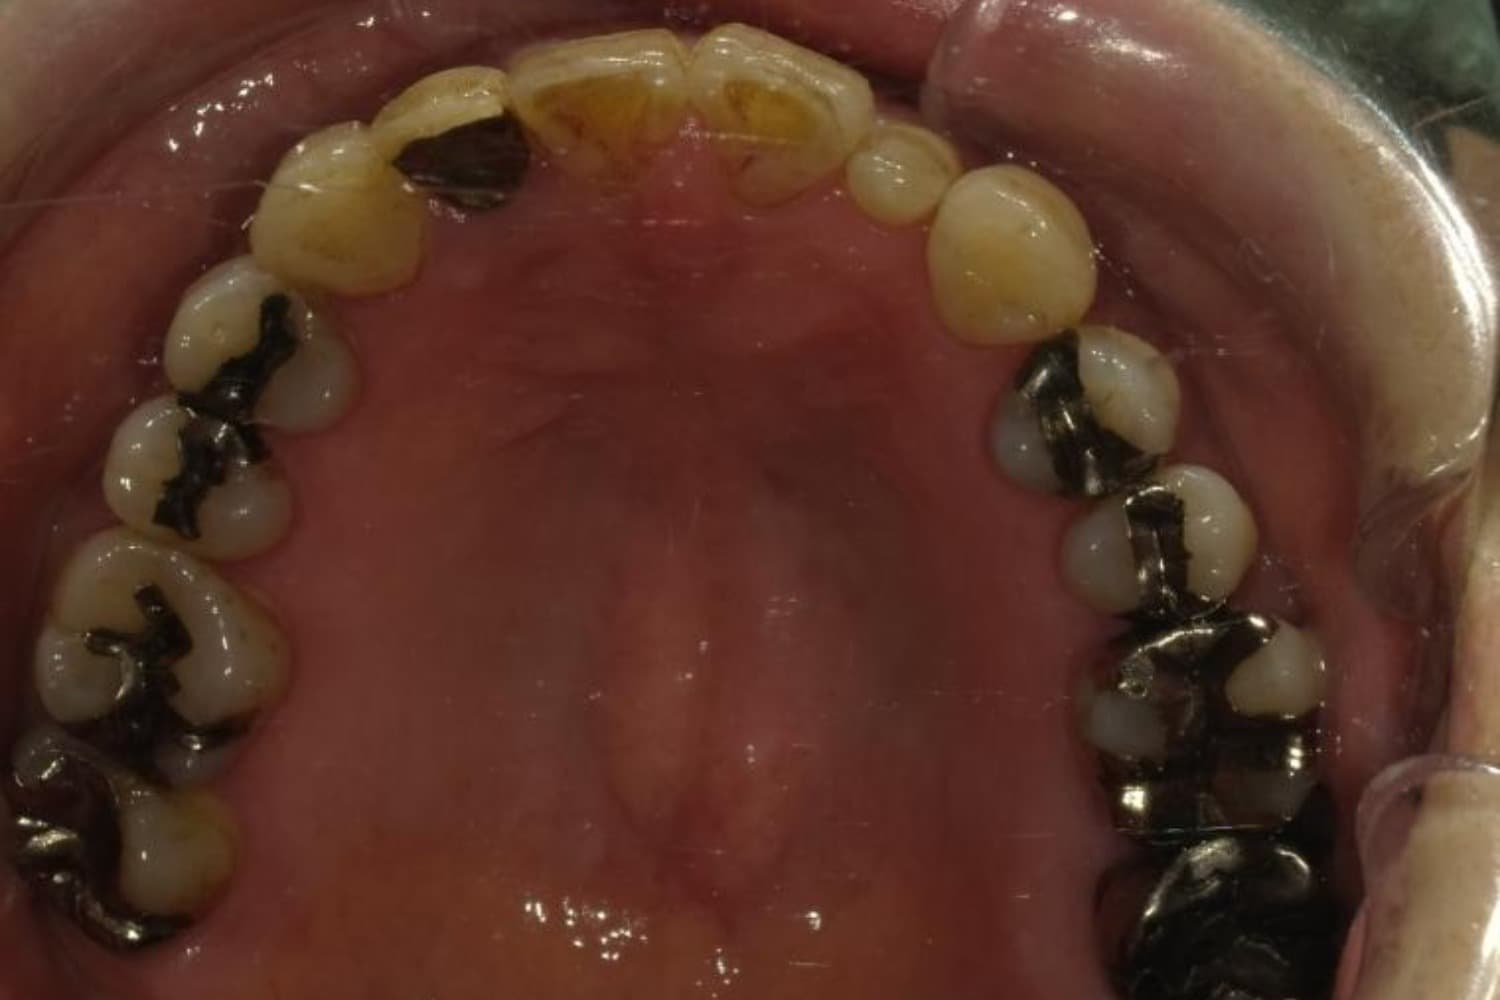

下顎大臼歯3本欠損症例

Before

After

左下第一大臼歯は保存が困難な状態であったため抜歯をおこないました。あわせて、ご来院時から欠損していた右下第一・第二大臼歯も含め、欠損部の補綴方法についてご説明し、インプラント治療を選択されました。

年齢

60歳

性別

男性

主訴

左下の第一大臼歯は別の医院で治療中でしたが、治療が思うように進まず、加えて他の箇所にも痛みが続いたことから、当院にご相談いただきました。

治療期間

10ヵ月

費用

140万円

副作用・リスク

インプラント治療は外科的な処置を伴い、多少の腫れや痛みが出ることがあります。 多くの場合は鎮痛薬で和らげることができます。